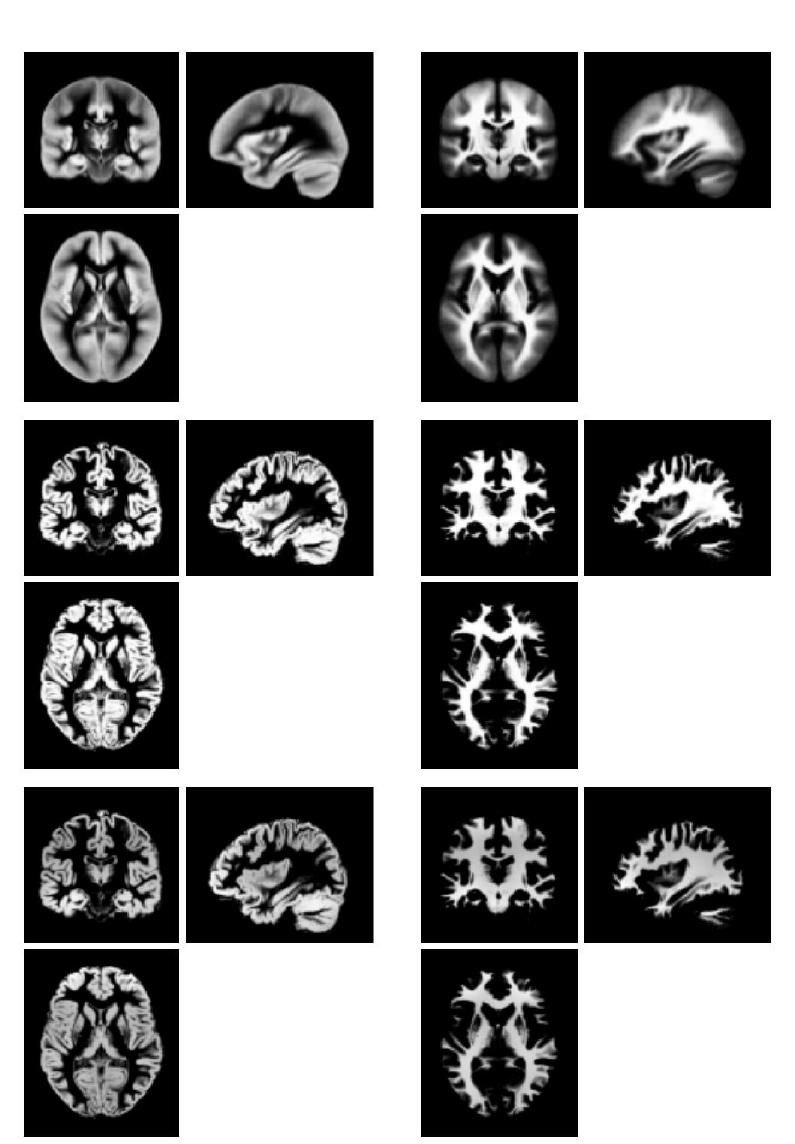

25 Dartel Tools 185

25.1 Initial Import .......................................186

25.1.1 Parameter Files ..................................186

25.1.2 Output Directory .................................187

25.1.3 Bounding box ...................................187

25.1.4 Voxel size .....................................187

25.1.5 Image option ...................................187

25.1.6 Grey Matter ...................................187

25.1.7 White Matter ...................................187

25.1.8 CSF ........................................187

47.1 Using Dartel for VBM ..................................471

47.1.1 Using Spatial→Segment .............................471